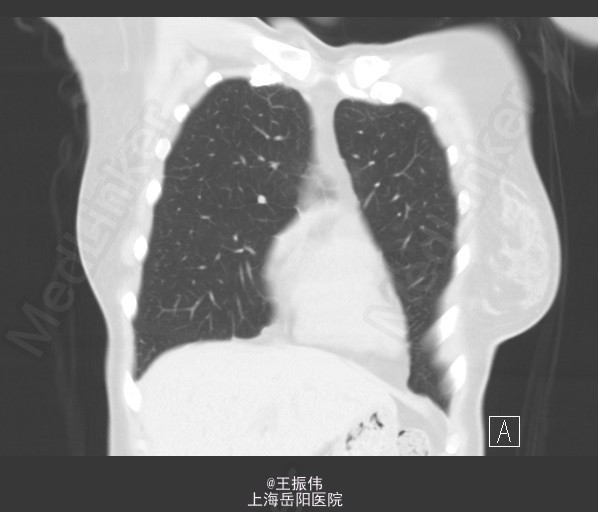

(6.23)胸部CT:两肺炎症已吸收,右中肺及两下肺条索影,请随访。